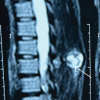

A 14-year-old school girl brought by her grandfather in June 2021 to the outpatient department with the complaints of slow-growing swelling on the left temporal region in scalp near left eye for 2 years. The swelling was small to begin with, which increased gradually over a period of 2 years to present size of 2*2 cm round-shaped swelling. Examination shows that the swelling was in the temporal fossa, above the zygomatic arch, smooth, not attached to overlying skin, becomes slightly less prominent on clenching of teeth, non-pulsatile, no transillumination, hard with no dilated veins over it and arising from bone. There were no other presenting symptoms. Hearing was normal. Parents of the patient were concerned with cosmesis only. She had been shown to an orthopedic surgeon 1 year back in July 2020 for the same complaint of swelling near left eye and had undergone 3D CT scan of skull where it showed bony outgrowth from the left temporal bone with features suggestive of exostosis. This bony outgrowth had cortex in continuity to cortex of temporal bone and medullary canal same as that of the temporal bone and ground-glass appearance (Figs. 1a, b, c).

Now, the patient was advised repeat CT scan with 3D reconstruction to look for increase in size and condition of underlying bone. Repeat CT scan showed (Fig. 1b) bony outgrowth of 35*28*22 mm arising from the left temporal bone with same cortical continuity and had pedicle. It was suggestive of pedunculated osteochondroma. There was no evidence of malignant transformation as swelling showed calcified osteoid-like mass throughout. Hence, the clinical and radiological diagnosis of the left temporal bone solitary osteochondroma was made. However, it is surprising to see absence of cartilage cap over the bony mass in both CT scans. As complaints were purely cosmesis, and relatives insisted surgical excision, surgery (extraperiosteal resection of solitary osteochondroma) was planned.